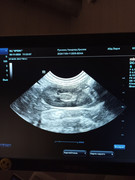

Сделали повторное узи 22.11. 2024 (первое было 09.11.2024). Высылаю фото и заключение.

Теперь ставят гидрометру и эндометрит. По мочевому мочекаменную.